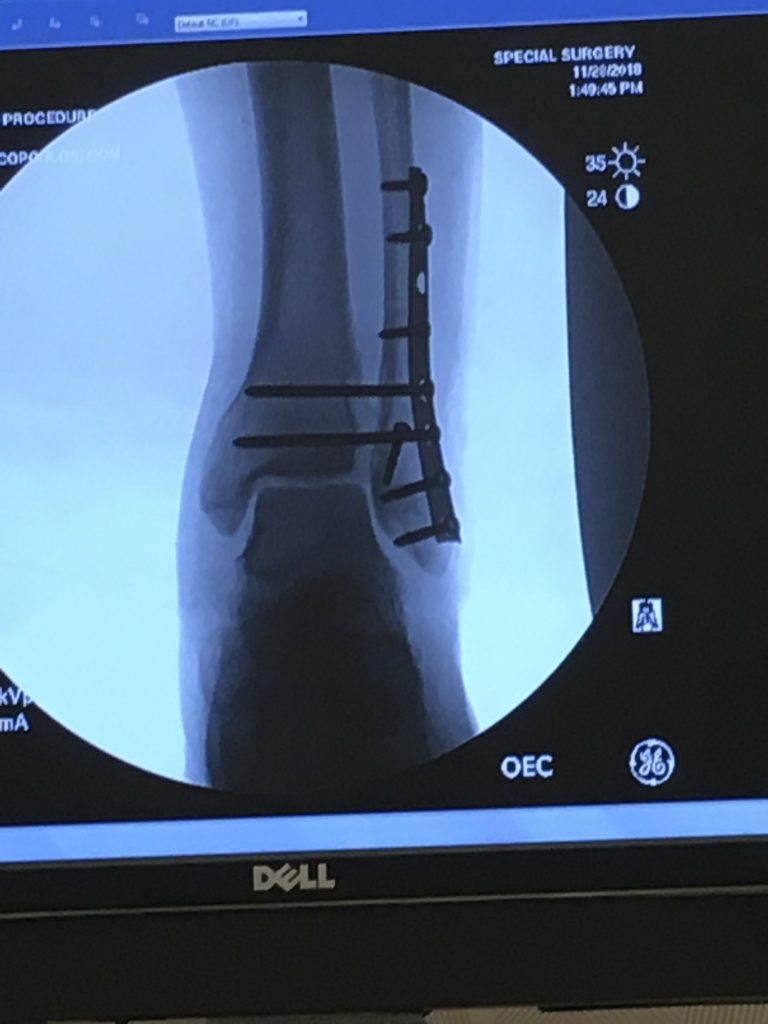

My life began to change when I met Dr. Demetracopoulos, Meghan, and Lowsant the next morning in HSS. An incredibly ideal team and part of the bigger, great HSS team and facility. Dr. D is a straight shooter - he told me right away that I would need 2-3 surgeries to insert and later remove at least some hardware. He suggested waiting a few days for surgery to give a ligament a chance to begin healing so as to avoid more complex surgery, which did happen. During my first surgery, he inserted a plate and 8 screws. I started PT in January and within 2 months I was on an anti-gravity treadmill (per Dr. D’s recommendation) and learned to walk without a limp.

But then one of my screws broke, so I had surgery again in March 2019, to replace the broken screw with Kevlar. Soon after, back to PT and I was back on a stationary bike by April and running slowly and briefly on a treadmill in July. I was taking spin classes 3-4 times per week to help with strength and balance (and even keeping up with the youngins in the classes). But then a tendon near the plate tore, so one more surgery in August 2019 to fix the tendon and take out the remaining hardware. Back to PT, I had 59 sessions in total, and repeated PT on my own the rest of each week.